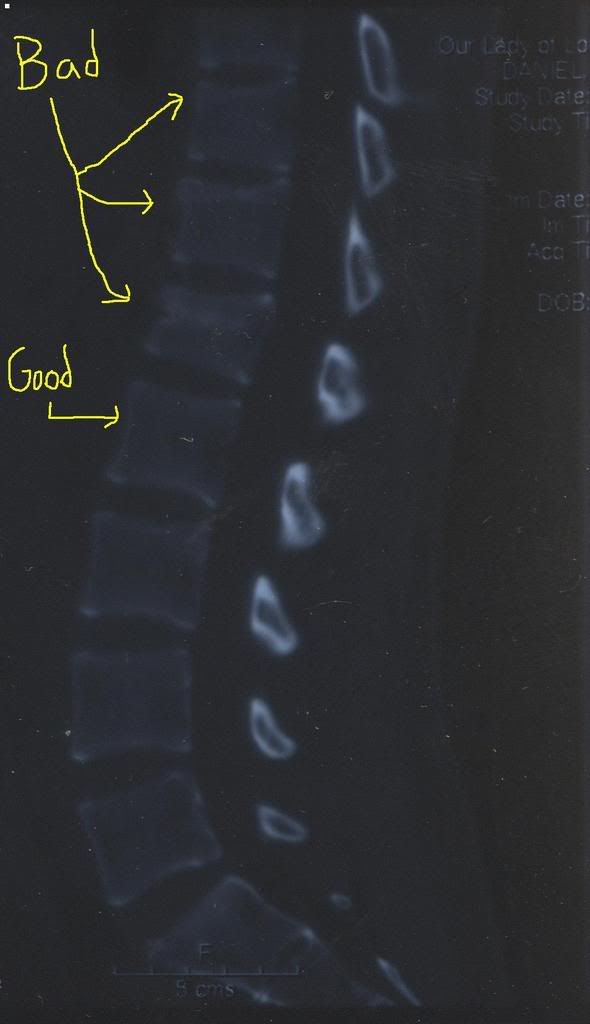

From when I broke my back.....